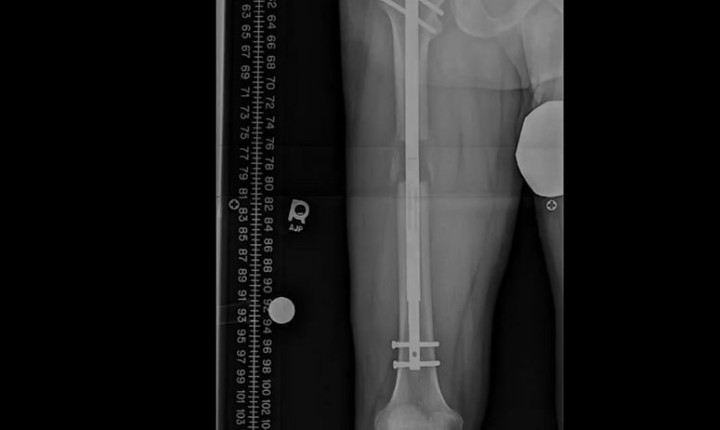

இந்த நிலையில், மேற்குலக நாடுகளில் மனிதர்களின் உயரத்தை அறுவை சிகிச்சையின் மூலம் கூட்டும் சிகிச்சைகள் அதிவேகமாக பிரபலமடைந்து வருகிறது. அதன் சாதக, பாதகங்களை இந்த காணொளி விளக்குகிறது.